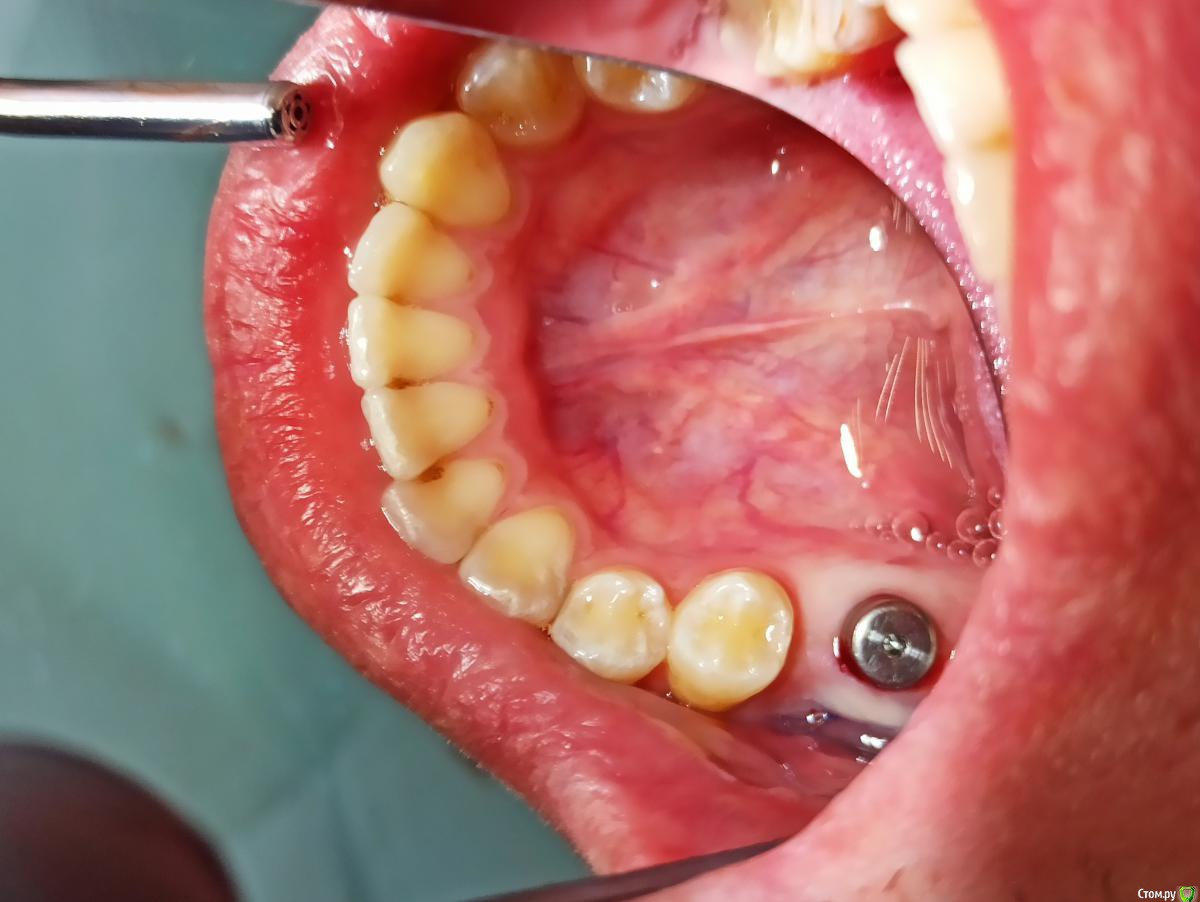

колесников Опубликовано 5 августа, 2020 Поделиться Опубликовано 5 августа, 2020 Ортопед оценивает с учетом будущей реставрации. Относительно моляра есть дефицит объёма гребня,но для имплантации объём костной ткани достаточный. Данный дефицит нивелируется дополнительной пластикой мягких тканей вестибулярно и земной с узкого на широкий фдм. Но мне кажется ,вы слишком язычно сместили платформу , и теперь решить проблему заменой на более широкий но стандартный фдм ,будет не просто,придётся делать индивидуальный. 1 Ссылка на комментарий

Irouil Опубликовано 6 августа, 2020 Поделиться Опубликовано 6 августа, 2020 Покажите рентген с винтом. Такое впечатление, что его позиция неудачная Ссылка на комментарий

колесников Опубликовано 6 августа, 2020 Поделиться Опубликовано 6 августа, 2020 Спасибо! А можно ли решить вопрос временной коронкой? Возможно в два этапа (постепенно добавляя объем вестибулярно композитом) Времянки буду делать сам определенно лучше делать через временную. Рентген бы не помешал,на каком уровне платформа?. Хорошо если вы делали редукцию гребня у платформы. Можно и за один раз ,но подсечь и сместить лоскут вестибулярно. 1 Ссылка на комментарий

MP1121 Опубликовано 7 августа, 2020 Автор Поделиться Опубликовано 7 августа, 2020 Но мне кажется ,вы слишком язычно сместили платформуДа, вы правы. Ссылка на комментарий